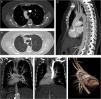

A 57-year-old female patient presented to our hospital with complaints difficulty in swallowing and coughing over the past 3 months. There was no history of fever, vomiting, nausea, or weight loss. She did not report any similar episode in the past. Chest X-ray showed the presence of dextrocardia. Contrast enhanced computed tomography (CT) scan was performed for detailed evaluation the hearth and mediastinal structures. The contrast enhanced CT examination showed aberrant left subclavian artery, right-sided aortic arch with dextrocardia, and variant azygos lobe on the left hemithorax (Fig. 1A–F). The aberrant left subclavian artery originated from the distal of the aortic arc was coursing through to posterior of the oesophagus. On the CT scan was seen total transposition of visceral organs so was confirmed that the patient have situs inversus totalis (Fig. 1D and E). All of visceral organs were seen on mirror image of normal locations. Situs inversus totalis is a rare congenial malformation that is incidentally detected in radiological evaluations. It is known as total transposition of abdominal and thoracic organs. Right sided aortic arch results from regression of the left dorsal aorta in embryologic development.1 If the aberrant left subclavian artery is found with the right-sided aortic arch, it is the last branch of the right-sided aortic arch. Although right sided aortic arch may be related to aberrant left subclavian artery,2 coincidence of situs inversus totalis and azygos lobe variant is extremely rare. Right aortic arch with aberrant left subclavian artery may be accompanied dextrocardia. Azygos lobe is a rare anatomic variant of right apical lobe,3 but on our case it was seen on left side because of situs inversus.

(A) Axial CT scan (mediastinal window) shows right-sided aortic arch. (B) Axial CT scan (parenchymal window) reveals a variant azygos lobe on the left hemithorax and aberrant left subclavian artery. (D and E) Coronal plan MIP CT images show total transposition of visceral organs accompanied with dextrocardia. (C, D and F) Sagittal, coronal and posterolateral projection 3D CT images show aberrant left subclavian artery originated from the distal of the right aortic arc. (E) Coronal MIP CT scan reveals origination and trace of the right and left carotid arteries.